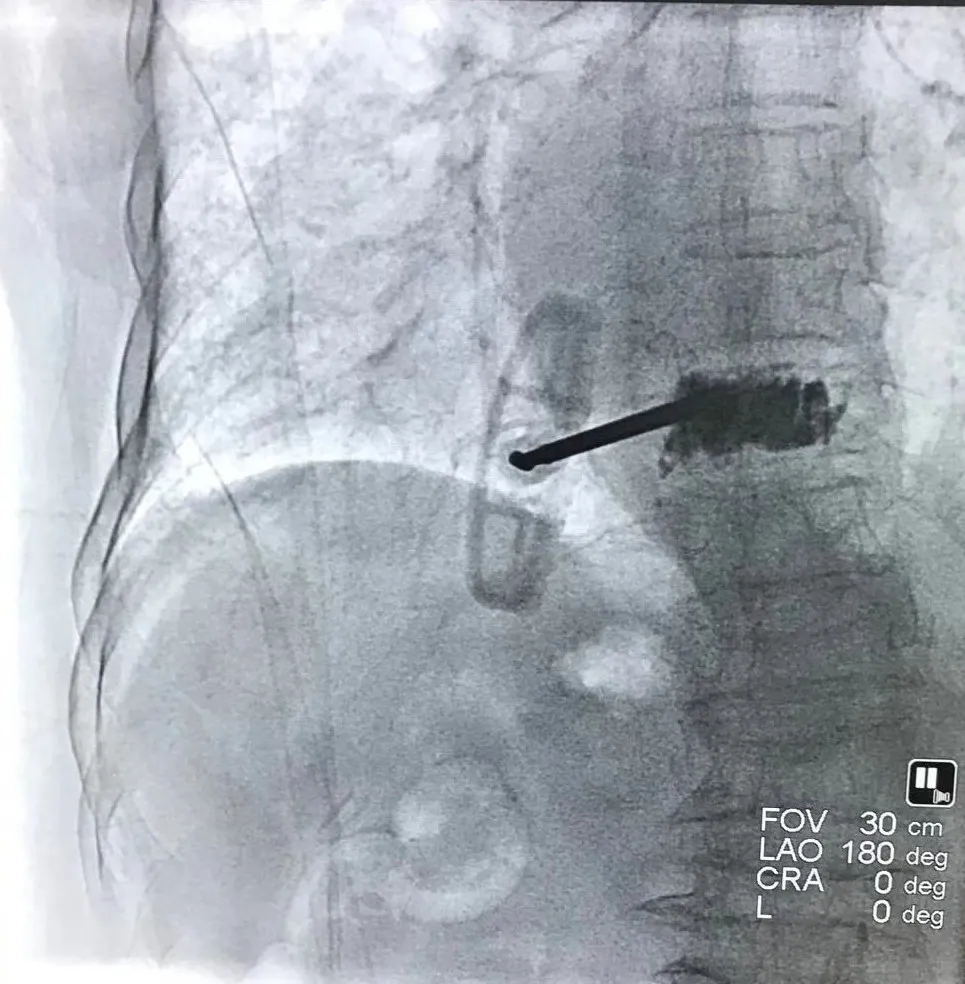

李奶奶畢竟已是高齡,身體機(jī)能處于衰退狀態(tài), 一次骨折就是一場生死考驗(yàn)。經(jīng)過與李奶奶本人及家屬充分溝通后,創(chuàng)傷外科孫守全主任團(tuán)隊(duì)分別于12月19日、21日行尺橈骨遠(yuǎn)端骨折切開復(fù)位內(nèi)固定術(shù)及胸9椎體壓縮性骨折椎體成形術(shù),手術(shù)順利,術(shù)后病情穩(wěn)定。

椎體成形術(shù)